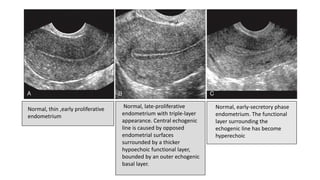

• The menstrual phase

endometrium consists of a

thin echogenic line.

• During the proliferative

phase, the endometrium

thickens, reaching 4 to 8 mm

• Periovulatory phase .

endometrium measures 6-

10mm and gives three layer

appearance

Normal, thin ,early proliferative

endometrium

Normal, late-proliferative

endometrium with triple-layer

appearance. Central echogenic

line is caused by opposed

endometrial surfaces

surrounded by a thicker

hypoechoic functional layer,

bounded by an outer echogenic

basal layer.

Normal, early-secretory phase

endometrium. The functional

layer surrounding the

echogenic line has become

hyperechoic

• Secretory phase.

The endometrium in this

phase measures 7 to 14

mm in thickness.